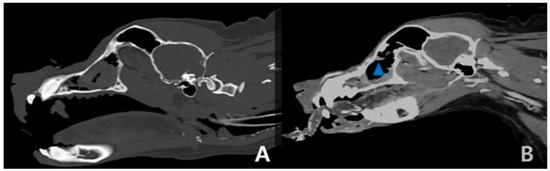

2. Case Description